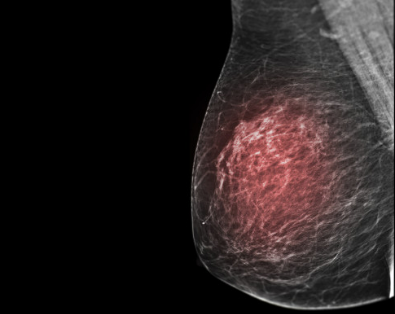

2.1  肿块

在两个相互垂直(或近似垂直)的投照位置上均能见到的有一定轮廓的占位性病变,仅在1个投照位置上见到,在其被确定具有三维占位特征之前,应描述为“不对称”。X线所见肿块并不一定与临床所触诊的肿块完全一致。

X线图像上所发现的肿块,临床不一定能够触及(因病灶太小、质软或腺体重叠形成伪影);临床所触及的肿块,X线图像上亦可能因为患者乳腺实质丰富而未能显示。

部分患者肿块周边伴有浸润和水肿,触诊常比X线图像所显示的肿块范围要大。肿块的描述包括边缘、形态和密度3个方面,其中肿块的边缘征象对判断肿块的性质最为重要。

2.1.1  肿块边缘描述

• 清楚:超过75%的肿块边界与周围正常组织分界清晰、锐利

• 遮蔽:超过25%的肿块边界被邻近的正常组织遮盖而无法对其作出进一步判断

• 小分叶:肿块边缘呈小波浪状改变

• 模糊:边缘与周边组织分界不清,但并非被周边正常组织遮盖所致

• 星芒状:从肿块边缘发出放射状线影

2.1.2  肿块形态描述

肿块形态描述包括圆形、卵圆形和不规则形。

2.1.3  肿块密度描述

以肿块与其周围相同体积的乳腺组织相比分为高、等、低(不含脂肪)和含脂肪密度4种。大多数乳腺癌呈高密度或等密度,极少数可呈低密度。